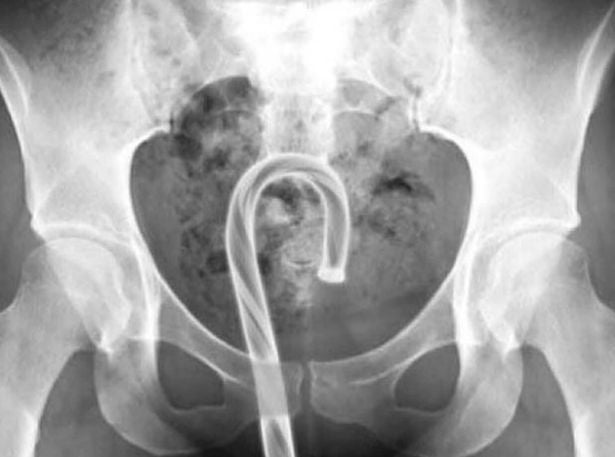

Eine Ärztin hat vor dem gefährlichen und "dummen" Trend gewarnt, mit Weihnachtsschmuck zu masturbieren. Dr. Sarah Welsh, eine Gynäkologin, sagte gegenüber NeedToKnow.Online, dass dieser Trend aus mehreren Gründen eine schlechte Idee sei, da Berichten zufolge Menschen in Folge dieser Handlung im Krankenhaus landeten.

Sie sagte: "Es ist nicht ratsam, mit Weihnachtsschmuck zu masturbieren". Die Mitbegründerin der Kondommarke Hanx fuhr fort: "Weihnachtsschmuck kann scharfe Kanten oder Teile haben, die bei der Masturbation abbrechen können, was zu Schmerzen führen kann, das Risiko eines Traumas birgt und generell für die Vagina ungeeignet ist". Einige Menschen haben Berichten zufolge süße Weihnachtsleckereien verwendet, um sich selbst zu befriedigen.

Die Gründe, warum dies keine gute Idee ist, sind vielfältig, sagt sie: "Aus hygienischen Gründen, aus Sorge, dass Stücke abbrechen könnten, oder wegen des Zuckergehalts von Süßigkeiten wie Zuckerstangen". Sie fügte hinzu: "Alles, was Zucker enthält, wie z. B. Weihnachtssüßigkeiten, sollte auch nicht in die Vagina gelangen, da dies das empfindliche Ökosystem des vaginalen Mikrobioms stört und zu vaginalen Soorinfektionen führen kann."